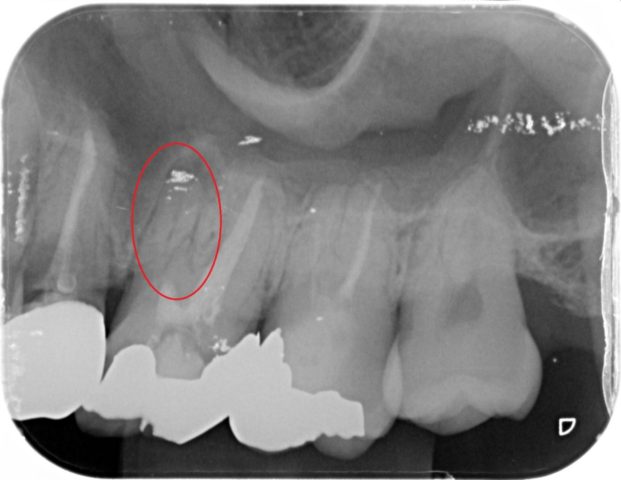

左上の奥歯が虫歯で欠けたという主訴で来られた患者さんです。

神経をすでに取っている歯だったため、痛みはありませんでしたが、根の治療が不十分でお薬が入っていない根があったため再治療を行いました。

その後、全体的な検査を行い、写真をお見せしながら治療の説明を行ったところ、